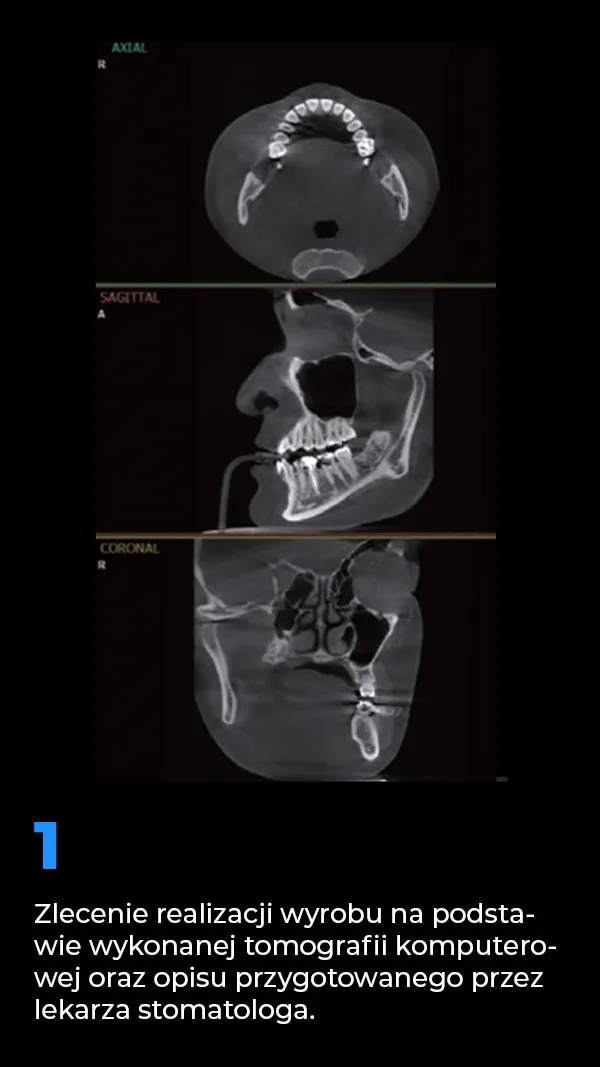

4. Schemat wytwarzania indywidualnych implantów podokostnowych

Schemat wytwarzania indywidualnych implantów podokosnowych MaiImplants.